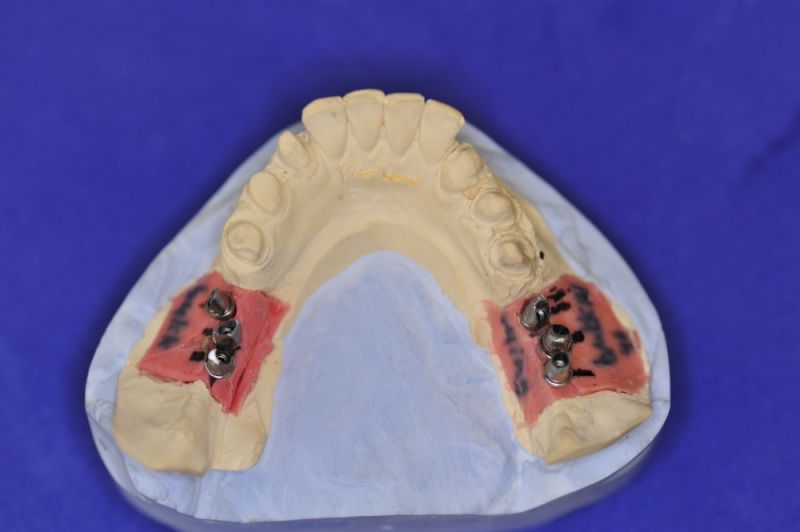

Geplant waren zwei Implantate in regio 6 und 7 des Unterkiefers. Trotz aller Planungen stellte sich intraoperativ heraus, dass zwei Implantate mit dem nötigen Durchmesser nicht in den extrem schmalen Kieferknochen des Unterkiefers einzubringen waren.

Also wurde intraoperativ umentschieden die Krafteinwirkung von geplanten zwei Normalimplantaten auf drei kleinere Implantate umzuleiten.

Es wurden sechs Implantate inseriert und diese wuchsen, trotz vielerlei Bedenken knöchern ein.

Nun stellte sich heraus, dass der Abstand zwischen den Implantaten sehr gering war, weil die Einschubrichtungen der Aufbauten sich zum Teil gegenseitig im Wege standen. Konfektionierte Teile mussten individuell umgeschliffen werden, dabei das Ziel, den Biss korrekt einzustellen nicht aus dem Auge zu verlieren.

Heute war nun Gerüsteinprobe, mit all den Problemen der Umsetzung zwischen Laborsituation und Mundsituation. Siehe Stichpunkt "Schnittstellenproblematik"! was bei Zähnen, auf Grund deren Eigenbeweglichkeit im Kieferkochen kein Problem wäre, ist bei drei unbeweglichen Implantaten ein Riesenproblem. Darüber spricht nur in aller Regel Niemand! Es musste viel fein nachgearbeitet werden.